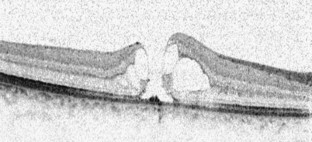

Abb. 1

Abb. 2

Abb. 3

Abb. 4

Abb. 5

Abb. 6

Bezüglich der optimalen Therapie des traumatischen Makulaforamens (TMF) gibt es keine Einigkeit. Wir berichten über den Spontanverschluss von TMF in 2 Fällen. Beim 1. Patienten führte der Verschluss zu einem Visusanstieg von 0,2 auf 0,8. Der 2. Patient zeigte trotz des Verschlusses wenige Tage nach dem Trauma keinen Visusanstieg. Dies ist vermutlich auf eine irreversible Schädigung von Photorezeptoren und retinalem Pigmentepithel zurückzuführen. Wegen der nicht seltenen Möglichkeit eines Spontanverschlusses von TMF hat eine abwartende Haltung bei diesem Krankheitsbild ihre Berechtigung.

The optimal treatment approach for traumatic macular holes (TMH) is still controversial. We report two cases of spontaneous closure of TMH. In the first patient, closure resulted in an increase in visual acuity from 0.2 to 0.8. In the second case, no increase in visual acuity was detectable despite spontaneous closure of the TMH within a few days after the trauma. This may be explained by an irreversible damage of the photoreceptors and retinal pigment epithelium. In patients with TMH, a waiting approach should be considered because of the possibility of spontaneous closure of TMHs.